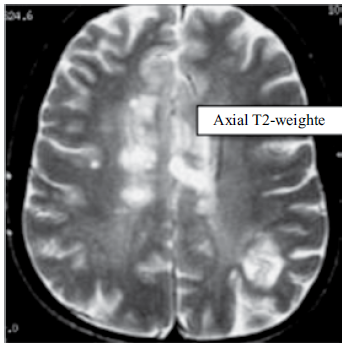

Paciente do sexo feminino, com 35 anos de idade, apresenta a ressonância magnética a seguir.

A hipótese diagnóstica é